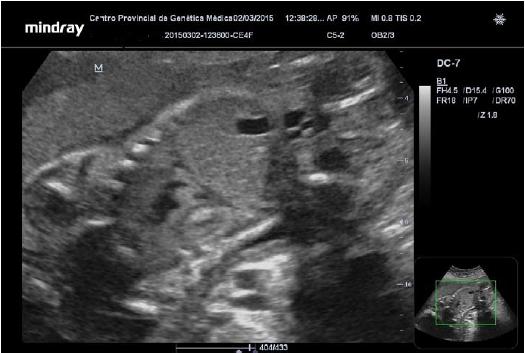

Se le realizó ultrasonido que informó: feto único, con buena vitalidad, líquido amniótico normal, placenta anterior. Nos llamó la atención la presencia de múltiples imágenes hiperecogénicas dentro del ventrículo izquierdo, ventrículo derecho y tabique interventricular que siguen los movimientos de contractilidad del musculo cardíaco; se localizó el mayor de esta imágenes en el tracto de salida del ventrículo izquierdo, sin otras alteraciones morfológicas fetales (Figuras 1).

Biometría:

DBP--- 64 mm - 26.1 semanas CC--- 239 mm - 26 semanas

CA--- 212 mm – 25.5 semanas LF--- 45mm – 25.1 semanas

Peso aproximado: 825 g

Edad gestacional probable: 25.5 semanas